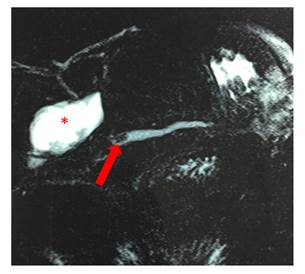

Durante los últimos episodios se realizó una Colangioresonancia (Figura 1) y 2 colangiopancreatografías endoscópicas retrógradas (CPER), los cuales evidenciaron una zona de estenosis del conducto de Wirsung a nivel del cuello y una litiasis de 6mm. En una primera instancia se realizó papilotomía, no logrando introducir un stent para franquear la estenosis, hecho que sí se logró en la segunda oportunidad.

Fig. 1: Colangio Resonancia que muestra la dilatación del conducto pancreático mayor con litiasis en su interior (flecha) y pseudoquiste pancreático(*).